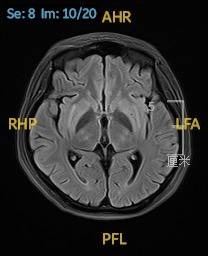

2023.02.09颅脑MR平扫示双侧基底节区及桥脑异常信号,考虑渗透性神经脱髓鞘综合征可能,脑桥部病灶较前范围增大,请结合临床,见图2。

图2 2023.02.09颅脑MR成像示双侧基底节区及桥脑见对称性片样长T1长T2信号,FLAIR呈高信号,较2023-01-18MR所示脑桥病灶范围增大。脑室、脑池、脑沟、脑裂未见明显异常。中线结构居中。